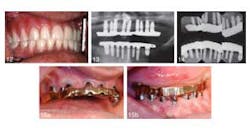

An article in the current issue of the Journal of Oral Implantology looks at long-term treatment for a patient with severe periodontal damage. The authors anticipate that the higher risk of implant failure in this patient will be offset by coating the implants with a rough, oxidized surface called TiUnite and by emphasizing the need for diligent oral hygiene. They also expect that by using overdenture prostheses instead of conventional removable dentures, they will improve stability and function — and thus patient satisfaction. Overall, increased use of implants has improved eating comfort and resulted in few complications after the surgery. However, pressure on implants is suspected to speed up loss of dense cortical bone in the jaw. Research has shown the TiUnite material stimulates bone growth, leading to faster fusion of implants and surrounding jawbone.RELATED | New material used in molar extraction sites optimizes bone regeneration and dental implant stability The current article is a case report on a 51-year-old patient who had been in a motorcycle accident and has a history of herpes, hepatitis, insulin-dependent diabetes, and persistent recurrent tooth decay. The patient’s remaining teeth (see photos below) were comprised of fractured crowns and older failing implants. The surgeons removed all of his teeth and old implants followed by the immediate insertions of new implants and stabilizing overdentures. Provisional implants were used for support during healing. Five months later, the interim provisional implants and prosthesis were removed and fabrication of a final restorative prosthesis was initiated.

RELATED | Atrophic patients have more options with new dental implant Despite the higher risk of implant failure due to his periodontal disease and diabetes, the patient’s implants have been in place for 12 years with no complications noted at routine checkups and cleanings. The patient has been instructed post surgery in proper use of floss threaders, deep-cleaning brushes, and an oral irrigator. His daily efforts to practice good oral hygiene improved his overall dental health. The patient was pleased with the results one week after the provisional implants were placed and was still happy with the surgery 12 years later. Little care and maintenance of the prostheses have been necessary.RELATED |Less invasive approach to dental implants allows heart patients to continue anticoagulation therapy